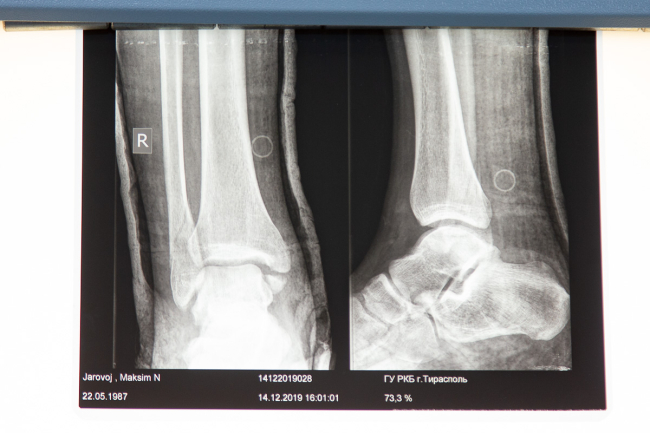

В кабинете, где проходит первичный осмотр, поставили негатоскоп: на светящемся экране врач может детально рассмотреть снимок из рентген-кабинета. Его уже не нужно распечатывать - доступна электронная версия.